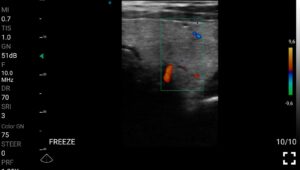

Οι ασύρματες κεφαλές MedBridge Echo Wave αναβαθμίζουν την ακρίβεια της διάγνωσης, διευκολύνει την ταχεία κλινική εκτίμηση και προσφέρει αυξημένη ασφάλεια κατά την εκτέλεση επεμβατικών διαδικασιών στον τομέα της Ενδοκρινολογίας.

Η χρήση των ασύρματων κεφαλων MedBridge Echo Wave, ειδικά σχεδιασμένης για ενδοκρινολογικές ιατρικές πράξεις, ενισχύουν περαιτέρω την κλινική ακρίβεια και την αποτελεσματικότητα της διαχείρισης των ασθενών. Οι κεφαλές MedBridge Echo Wave επιτρέπουν την καθοδήγηση διαγνωστικών και θεραπευτικών παρεμβάσεων, όπως παρακεντήσεις και βιοψίες, τον ακριβή εντοπισμό και τη μορφολογική αξιολόγηση νεοπλασματικών αλλοιώσεων, καθώς και την παρακολούθηση της ανταπόκρισης στη θεραπεία. Παράλληλα, διευκολύνει τη διενέργεια ελάχιστα επεμβατικών πράξεων, προσφέροντας υψηλά επίπεδα ασφάλειας και ακρίβειας.

Ολες οι παραπάνω απεικονιστικές εξετάσεις έχουν ληφθεί από φορητή συσκευή όπως: Apple Iphone, Tablet, Samsung Mobile Phones και διάφορες άλλες φορητές συσκευές.